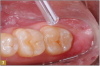

Giomer restoratives are bioactive regenerative materials that can be used where traditional direct composite materials are indicated. In the case presented in Figure 1, decay was noted on the occlusal surfaces of a first and second molar. What often looks like a very small amount of decay on the surface can lead to the discovery of significant dentin destruction. The quadrant was isolated and air abrasion was performed using 50 µm aluminum oxide (Figure 2). The occlusal groove enamel was abraded, revealing obvious decay to the dentin (Figure 3). Decay was identified with caries indicator and removed with a #2 round bur and slow-speed handpiece, with the goal of preserving as much healthy tooth structure as possible (Figure 4). Caries indicator stains denatured collagen and debris and helps to identify areas needing attention by the dentist, but equally importantly, it identifies areas without damage that can be preserved.

Fig 3. On the second molar, a #2 dental bur was used on a slow speed.

Figure 3